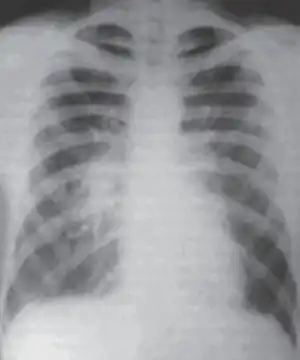

| CXR of atypical pneumonia showing right central peribronchial infiltrate | |

Chest X-rays often show a lung infection before physical signs are observable.[11] This is occult pneumonia. In general, occult pneumonia is rather often present in patients with pneumonia and can also be caused by Streptococcus pneumoniae, as the decrease of occult pneumonia after vaccination of children with a pneumococcal vaccine suggests.[18][19]

Infiltration commonly begins in the perihilar region (where the bronchus begins) and spreads in a wedge- or fan-shaped fashion toward the periphery of the lung field. The process most often involves the lower lobe, but may affect any lobe or combination of lobes.[11]